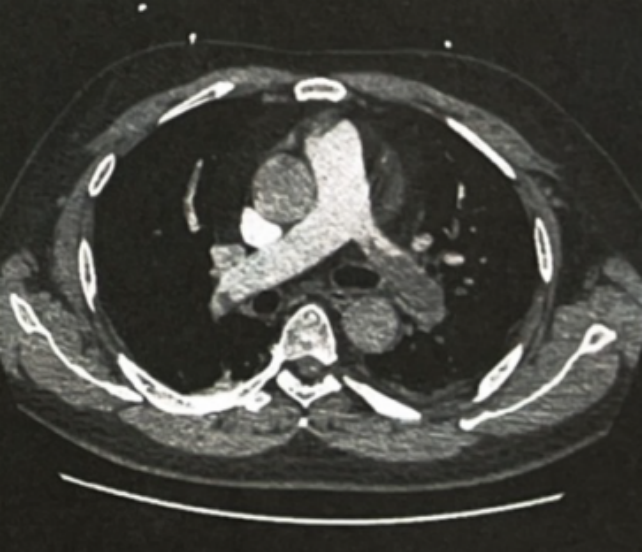

图1. CTPA

床旁UCG示右室偏大,室间隔运动略僵硬,肺动脉收缩压35mmHg,肺栓塞诊断明确。予r-tPA 100mg溶栓,序贯予低分子肝素钙注射液及华法林抗凝治疗,患者胸闷、咯血、咳嗽等症状逐渐消失。同时给予泼尼松联合环孢素A治疗肾病综合征半年,其间环孢素A的浓度维持在125~175ng/ml,肾病综合征一直没有缓解,遂停药。复查UTP 7~10g/d,ALB 16~18g/L,换用泼尼松联合环磷酰胺治疗。其间持续服用华法林,维持INR 2.0~2.8。2个月后患者UTP 3.5g/d,ALB 28g/L,泼尼松减量。3个月后患者UTP 2.1g/d,ALB 32g/L,泼尼松继续减量;环磷酰胺累积剂量达到9g后停药;拟继续服药华法林6个月。